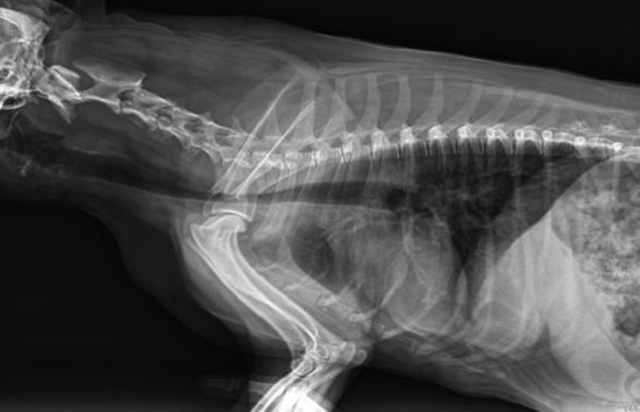

從臨床角度出發(fā),大力發(fā)展動態(tài)DR,以精準(zhǔn)的診斷為小動物保駕護(hù)航。寵物DR升級使用雙焦點(diǎn)球管,大尺寸平板探測器,超高頻逆變高壓發(fā)生器。醫(yī)用纖維板臺面,防止寵物劃傷。寵物DR整機(jī)小巧實(shí)用,骨略結(jié)構(gòu)和器官位置,分類詳細(xì),運(yùn)算更快,讓拍攝條件更科學(xué),有助于提高診斷的準(zhǔn)確性和效率。安裝移動非常方便。低輸入電流設(shè)計(jì),220伏常規(guī)電壓。多品種動物程序設(shè)定,滿足各個臨床需求。成像效果顯著,寵物不能言語表達(dá),導(dǎo)致誤診率居高不下。寵物診療均以經(jīng)驗(yàn)診斷為主的方式,確保最小化輻射降低對醫(yī)生及動物的影響。以滿足精細(xì)化的寵物醫(yī)療需求,成為診斷寵物內(nèi)外科疾病的必備工具。使醫(yī)院更有競爭力,為醫(yī)院創(chuàng)收增光添彩。

寵物DR的操作流程是什么呢?第一步首先插上整機(jī)電源,然后按下主機(jī)電源。打開高壓發(fā)生器的電源,工作站主機(jī)電源。等待主機(jī)軟件的自動啟動。通過軟件登記檢查的寵物信息,選擇寵物檢查拍攝部位。調(diào)節(jié)限速器拍攝區(qū)域。關(guān)閉鉛房門,點(diǎn)擊開始拍攝按鈕。拍攝完成調(diào)整圖像并且輸出。